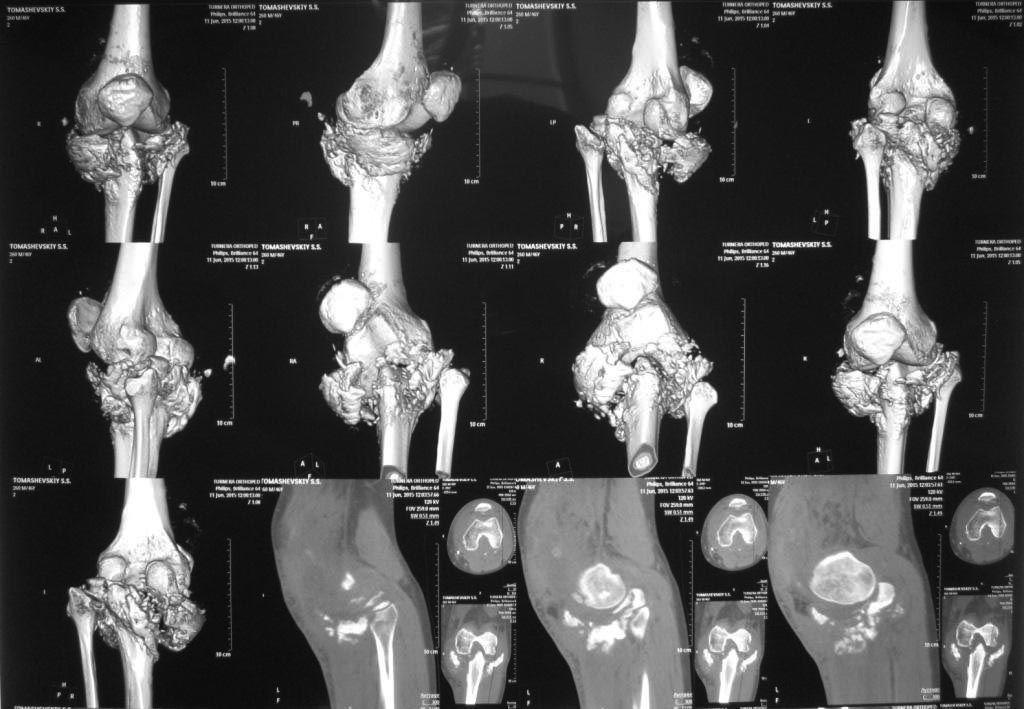

КТ сложного перелома TIBIA

Михаил Кислицын 16 Июнь 2015, 17:38

Пациент выполнил КТ коленного сустава. У кого как-то изменилось мнение про тактику, пожалуйста, напишите. Спасибо

• Re: КТ сложного перелома TIBIA

Отправитель: Maxim Agalakov 17 Июнь 2015, 12:40

для меня ничего не прояснилось в плане диагноза, соответственно и тактики. В перелом не очень верится, для спонтанного остеонекроза слишком уж большой масштаб разрушений, для туберкулезного и септического артрита картинка не слишком характерна (бедро почти интактно). Может быть Charcot joint или Secondary Osteonecrosis of the Knee? Может быть эти статьи вам помогут